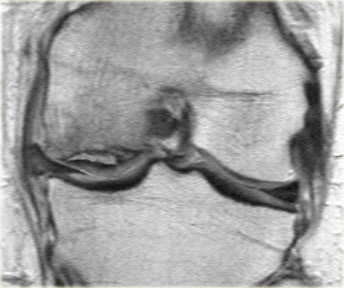

Bên trái là các hình ảnh PD sagittal của một trường hợp sụn chêm lật.

Toàn bộ sừng sau bị lật ra phía trước, tạo ra dấu hiệu sụn chêm rỗng (empty meniscus sign) (mũi tên).